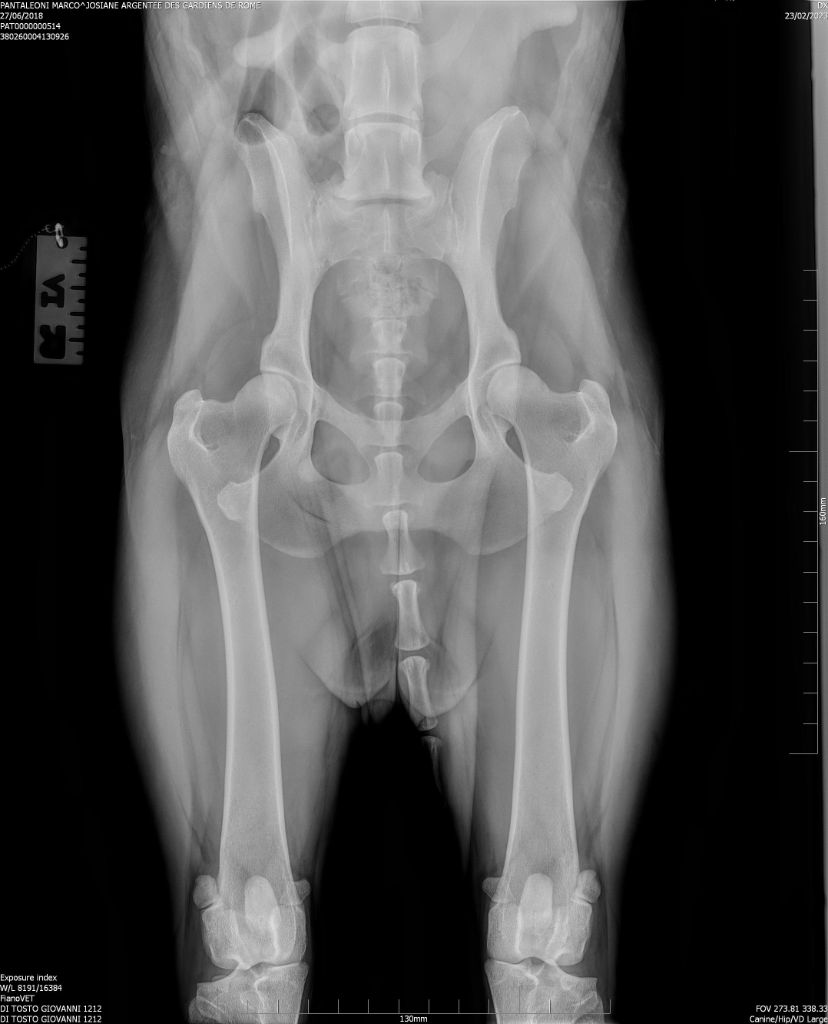

Josiane argentee Des Gardiens De Rome

Berger de Beauce

27/06/2018

| Tatouage | 380260004130926 |